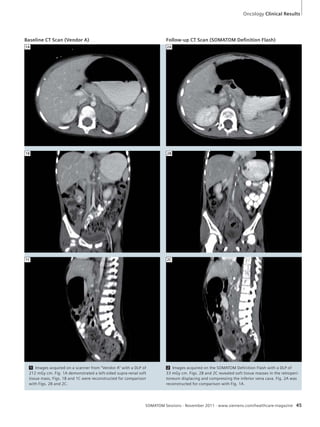

the intimal flaps, especially in the

ascending aorta and aortic arch. This was

improved when the ECG-gated spiral

scanning was introduced. However, it

had to be performed at the costs of slower

scanning and associated higher radiation

dose. A new scanner with a new scan-ning

technique improved that – the

SOMATOM Definition Flash scanner and

its Flash scanning protocols. In this case it